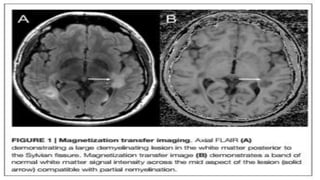

Magnetization Transfer Imaging

Remyelinated lesions have higher MTR than unmyelinated lesions, and

lower than NAWM .